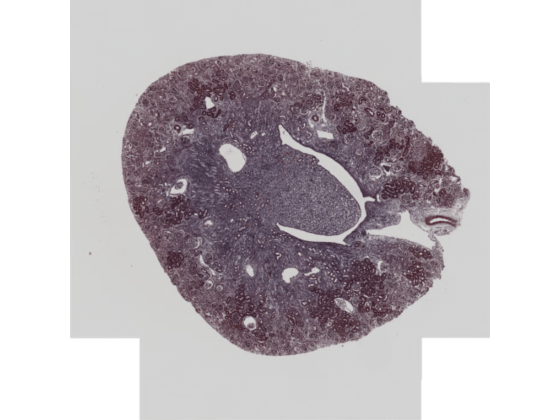

Run this code to download a whole slide image from the MathWorks website and unzip the downloaded folder. The image is available in the OpenSlide library test data set [2]. The file is in the CZI format, which is associated with ZEISS microscope cameras. The image shows trichrome stain on a mouse kidney sample.

imageshow(bimSeries(1))